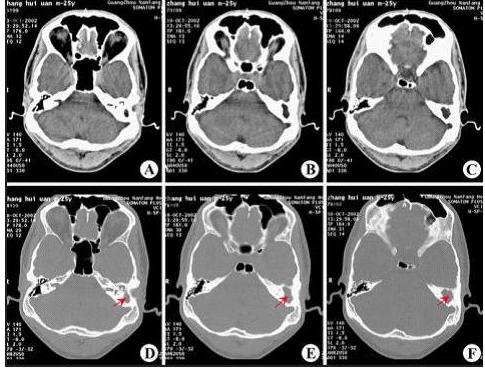

CT显示:左侧慢性中耳乳突炎(胆脂瘤型)